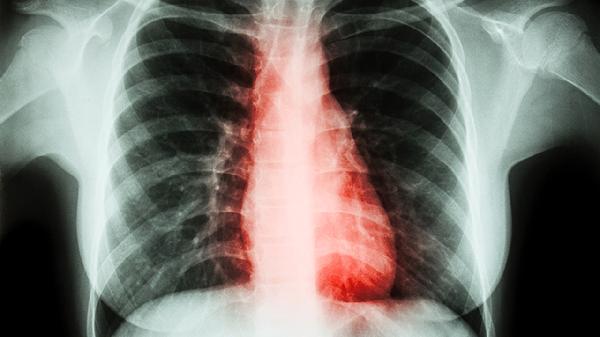

3、改善肺部不适

清肺化痰丸能够减轻肺部炎症反应,舒缓支气管痉挛,从而缓解咳嗽、气促及胸痛等伴随症状。对于肺热亢盛导致的咽喉肿痛、呼吸不畅也有辅助改善效果。

4、调节肺功能

药物中的有效成分可帮助恢复肺部正常生理状态,改善换气功能,减少痰液对呼吸道的阻塞。长期肺热不清导致的呼吸费力、喘息声重等症状可能获得改善。

5、辅助治疗作用

在支气管炎、肺炎等疾病治疗过程中,清肺化痰丸可作为辅助用药帮助控制症状。但需注意其不能替代抗菌药物等针对性治疗,应在医生指导下配合使用。